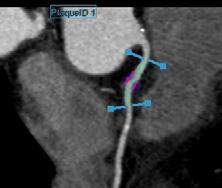

Un alt algoritm este dedicat IRMului cerebral, unde realizează volumetria structurilor encefalice și evidențiază leziuni demielinizante, aspecte esențiale pentru diagnosticul și monitorizarea bolilor neurodegenerative, precum scleroza multiplă. <figurile 2, 3, 4, 5> Un avantaj major îl constituie posibilitatea de a efectua comparații longitudinale între examene succesive, facilitând evaluarea dinamică a progresiei bolii sau a răspunsului la tratament, prin cuantificarea modificărilor de volum sau a numărului de leziuni. De asemenea, utilizăm instrumente de IA dedicate angio-IRM, capabile să identifice automat anevrismele cerebrale și să ofere informații privind dimensiunea, localizarea acestora și urmărirea în timp a acestor leziuni vasculare, oferind medicului posibilitatea de a aprecia evoluția și de a decide conduita optimă. <figura 6> În domeniul imagisticii prostatei, un